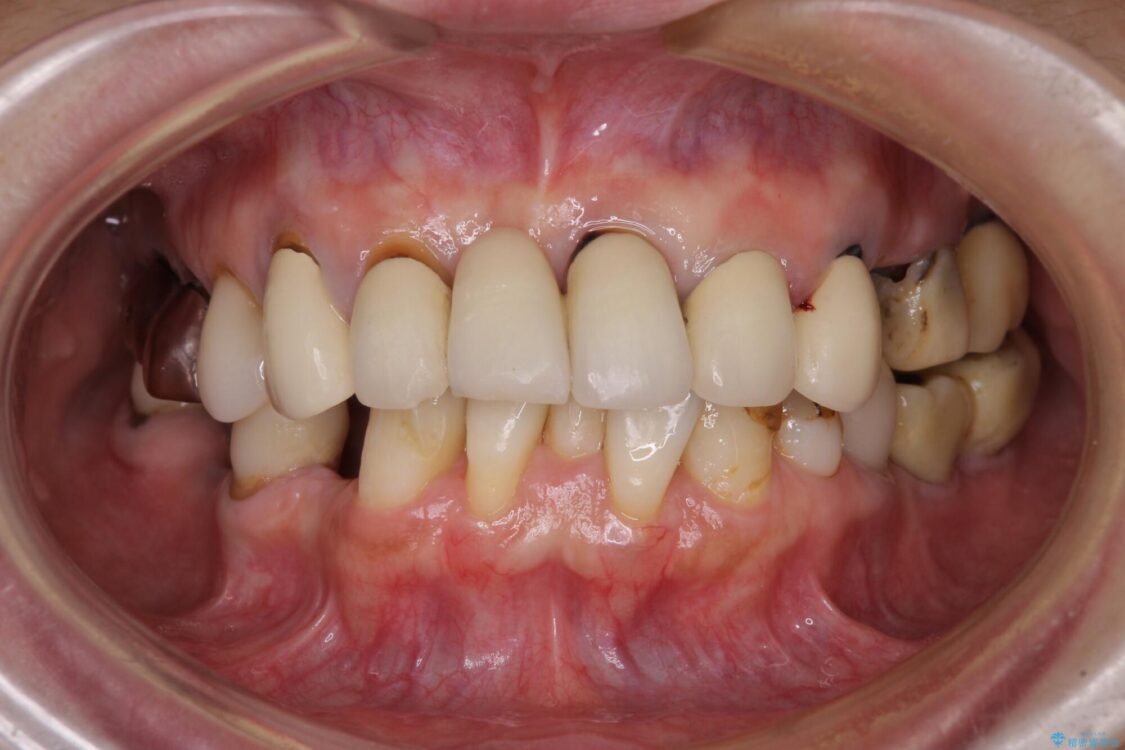

治療前

• 放置したインプラントとインビザライン 全顎リカバリー治療 治療前画像